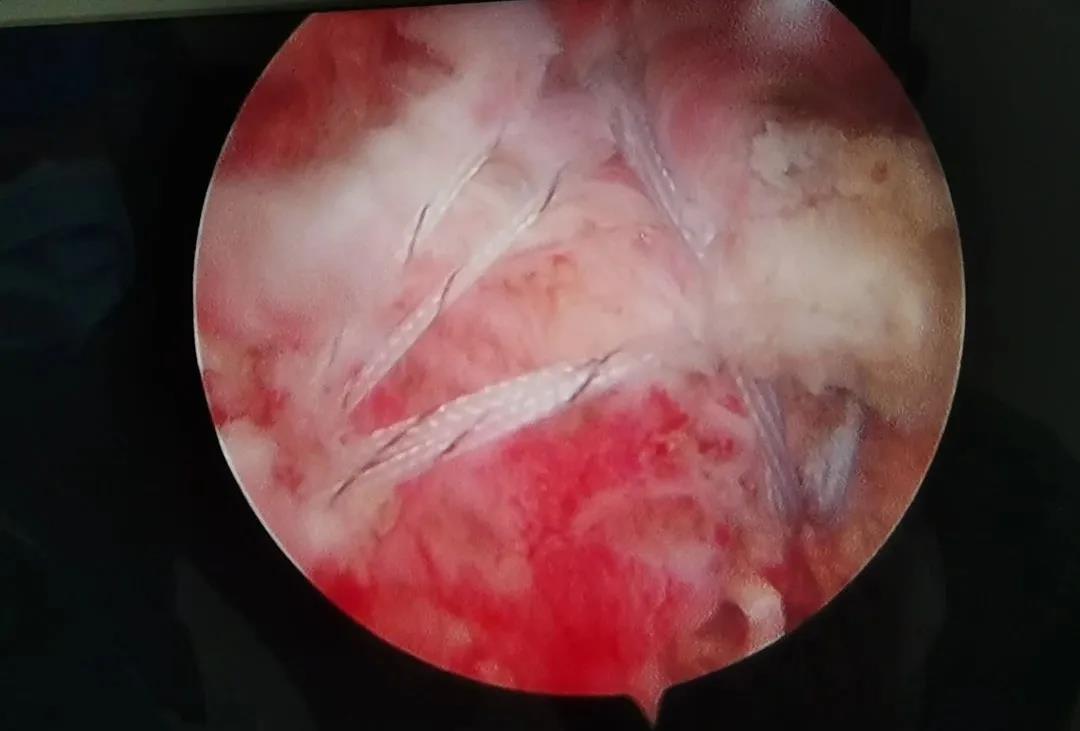

骨二科巨大肩袖撕裂關(guān)節(jié)鏡雙排縫合固定術(shù)

中年男性患者羅先生,因受到外傷后左肩部疼痛,連續(xù)3天活動(dòng)不便,3月25日來(lái)到我院就診,經(jīng)檢查,羅先生被診斷為左肩袖損傷,需要進(jìn)行手術(shù)治療。經(jīng)過(guò)精密的術(shù)前準(zhǔn)備,27日,骨二科主任許冬雷為患者實(shí)施了巨大肩袖撕裂關(guān)節(jié)鏡雙排縫合固定手術(shù),手術(shù)成功,術(shù)后病人恢復(fù)理想。